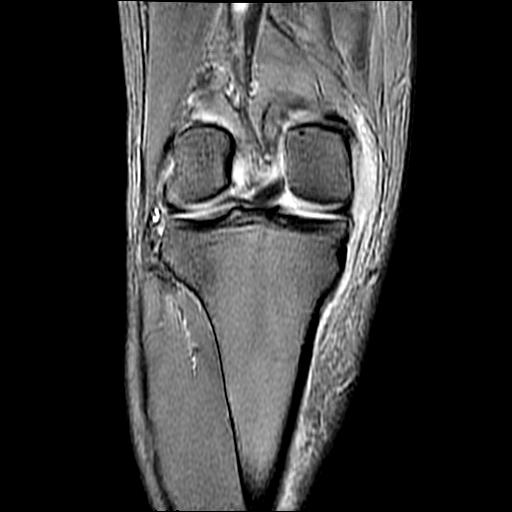

40岁男性,右膝关节外伤,x光平片示,髁间隆突撕脱骨折。

1、前交叉韧带撕裂;

2、外侧半月板后角撕裂;

3、关节腔积液。

髁间隆突撕脱骨折;内侧副韧带损伤。

1、内侧副韧带撕裂;

2、前交叉韧带撕裂;

3、滑膜炎伴关节腔积液。

内侧副韧带撕裂及关节腔积液是肯定的,但是前交叉撕裂确定吗?会不会有容积效应的因素,因为前一张前交叉显示清楚,连续性良好,且较光滑。请问楼主有关节镜支持吗?我们医院也经常有这样的患者,但苦于没有关节镜,而无法对照、证实(除非完全断裂),出现了不同的诊断结果只能毫无意义的争论。

1、前交叉韧、内侧副韧带撕裂;

3、关节腔积液。4、髁间脊撕脱骨折。